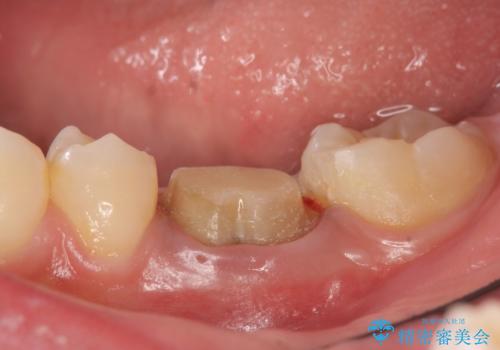

- 他院にて治療途中の歯を診て欲しいといらっしゃった方の症例です。

X線上で根尖病変を認めたため再根管治療を行い、オールセラミッククラウンによる補綴を行いました。